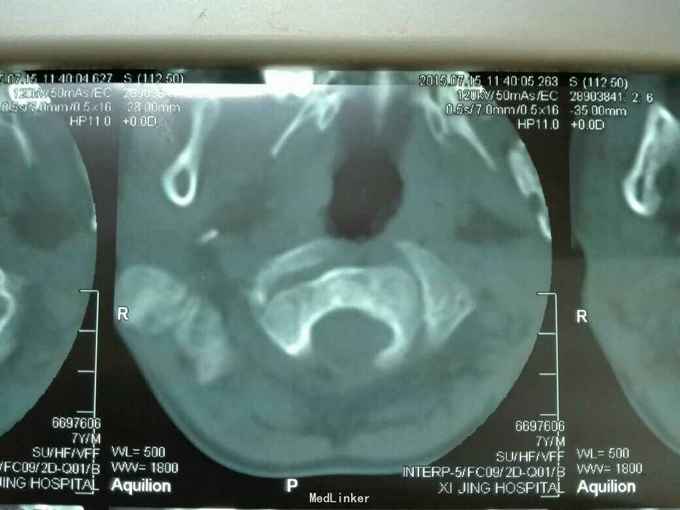

先天脊柱畸形

先天脊柱畸形8年。